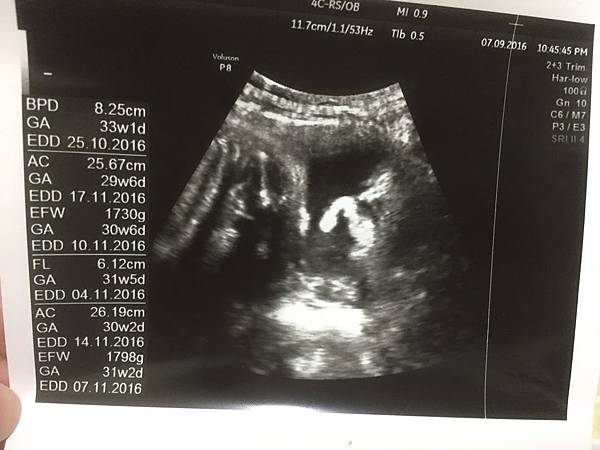

32週產檢,葉黃素體重來到1800公克~比上次足足多了500!

然後超音波照第一張我依然也是看不懂那到底是什麼

哈哈哈以後要是葉黃素問我我還真是回答不出來

這張很白癡想說記錄一下葉黃素的體重